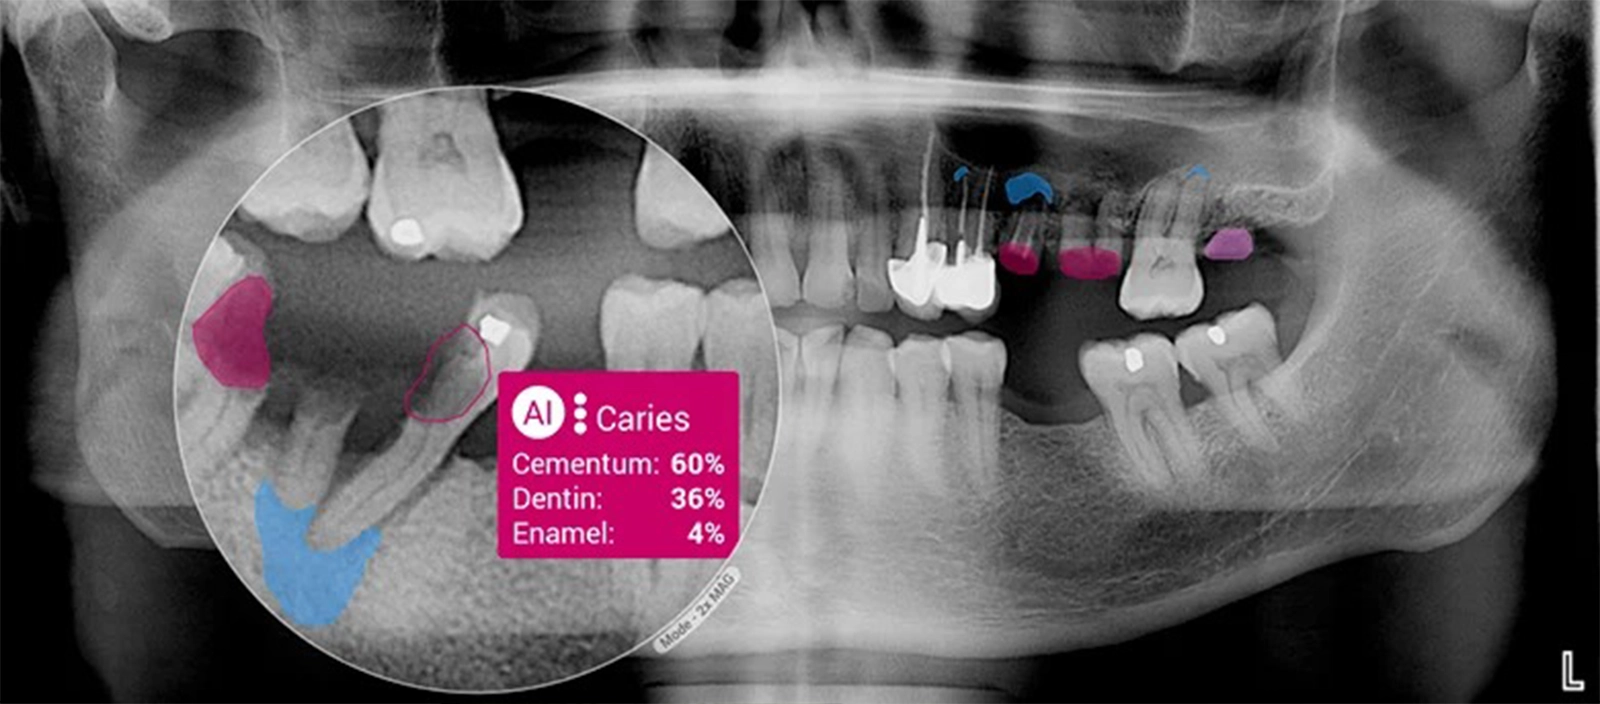

Deep learning models are especially well-suited to analysing dental images, including bitewing and periapical radiographs, panoramic X-rays, and three-dimensional scans. When trained on large, high-quality datasets, they can detect subtle features linked to tooth decay, bone loss, and anatomical variations that may be difficult to identify consistently with the human eye alone.

AI Dental Pathology Detection, Planmeca, Second Opinion®

In restorative dentistry, AI is being studied for its ability to detect and classify dental caries, assess restoration margins, and identify existing restorations such as fillings and crowns on radiographs. For certain image-based tasks, research indicates that AI performance can be comparable to that of trained clinicians.

These systems are designed to enhance diagnostic consistency and support early intervention, while clinical judgement and decision-making remain firmly with the dentist.